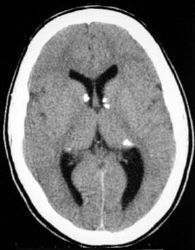

Test 17  (phakomatoses)

Refer to the pictures above for question 1 & 2

1. Other ocular manifestations of the above condition

include:

2. Other manifestations of this condition include: